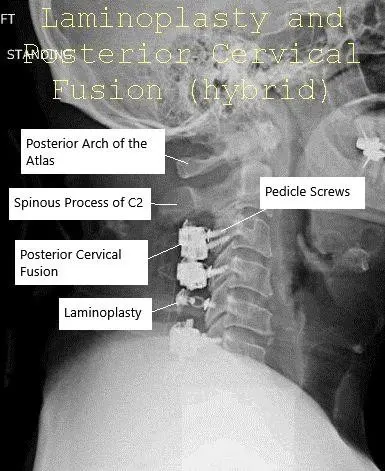

AP and Lateral view X-ray Post-op Laminoplasty and Posterior Spinal Fusion